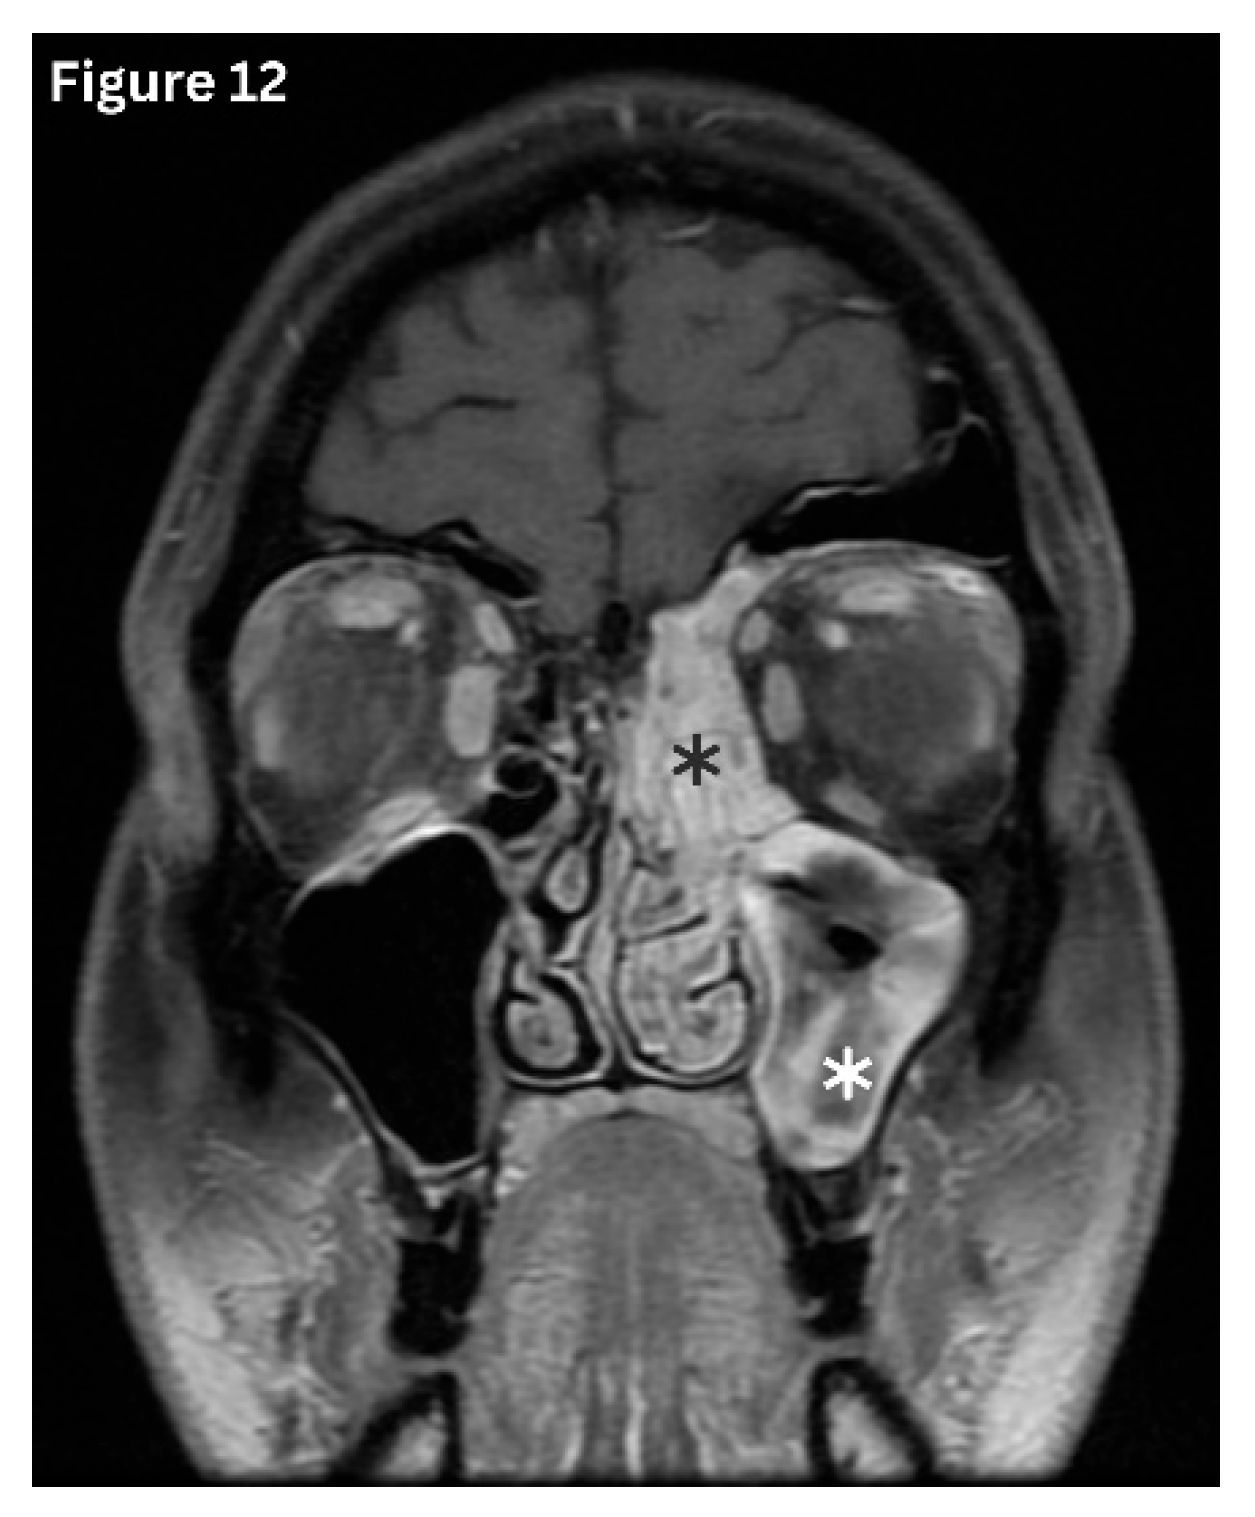

Acute sinusitis typically demonstrates air–fluid levels, diffuse mucosal thickening, and narrowing of the sinus drainage pathways on imaging. (Figure 11) Chronic sinusitis develops over several months and is characterised by persistent polypoid mucosal thickening, bony remodelling, and sclerosis of the sinus walls on sinus HRCT. (Figure 12 and Figure 13) Allergic fungal rhinosinusitis is characterised by expanded sinuses containing centrally hyperdense inspissated mucin, accompanied by a peripheral hypodense mucosal rim, often in association with nasal polyps, as seen on HRCT. Recurrent and subacute sinusitis exhibits overlapping features of both acute and chronic disease. This is often associated with partial ostial obstruction or underlying anatomical variations [5,16].

Figure 12. Coronal MRI- T2 image shows significant mucosal thickening in the left maxillary and ethmoid sinuses consistent with chronic rhinosinusitis.